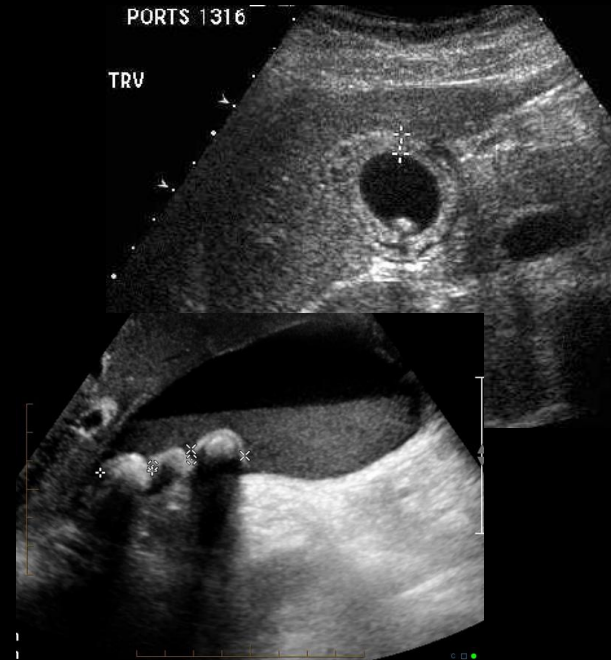

Medidas

- Volumen vesicular:

- Pared vesicular:

• < 100 ml

• < 3 mm

¿Qué signo ecográfico es típico de litos vesiculares?

Sombra sónica posterior (HIPERECOGENICIDADES)